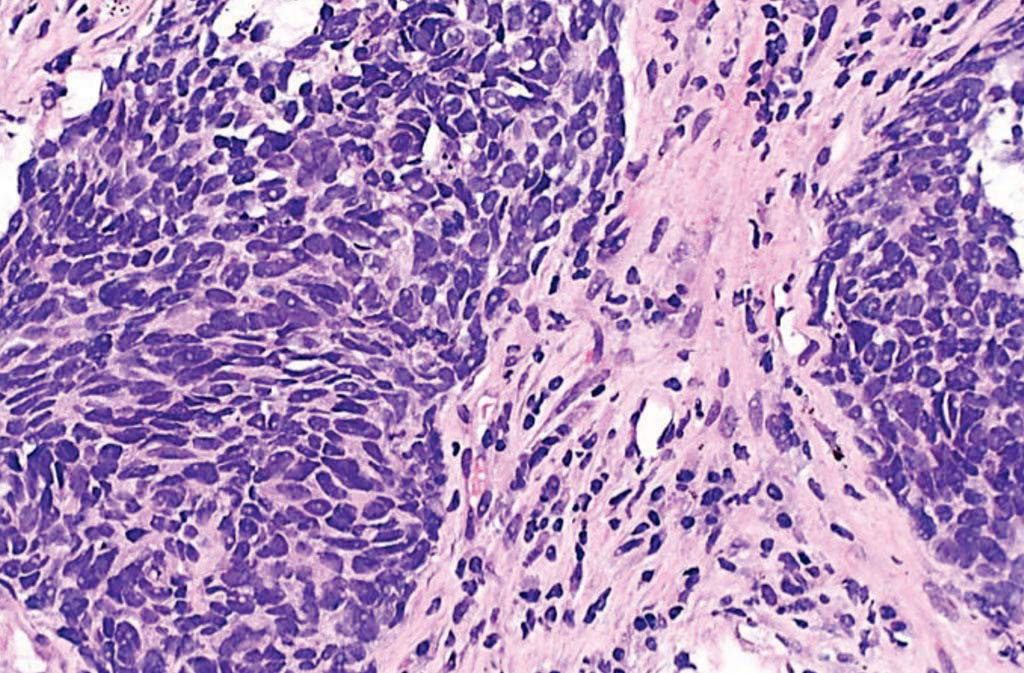

图片:非小细胞肺癌的组织病理学(照片由Librepath提供)。